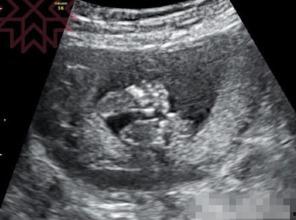

首先得说,德国产检B超视频的画质真的是没得挑。高清的画质让每一个细节都清晰可见,宝宝的小手、小脚、小脸蛋,还有那些血管、器官,都仿佛就在眼前。这种画质让人仿佛能感受到宝宝在妈妈肚子里的呼吸和心跳,真是太神奇了!

德国产检B超视频还展示了科技在医疗领域的应用。先进的B超设备可以实时监测宝宝的发育情况,医生可以通过数据分析,为孕妇提供更精准的指导。这种科技助力,让产检更加科学、高效。